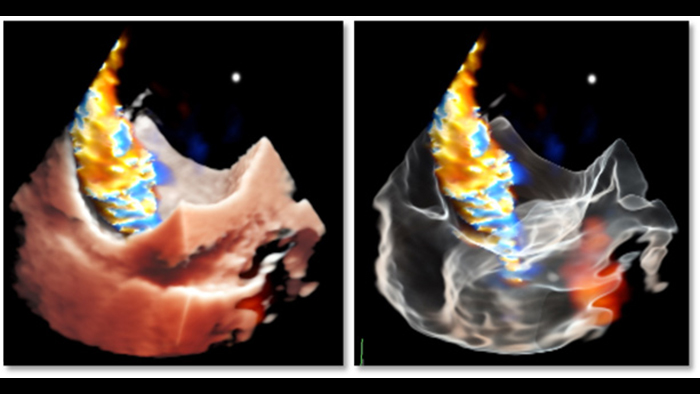

Deep insights with TrueVue color and GlassVue

Cardiac TrueVue photorealistic rendering with MultiVue image alignment